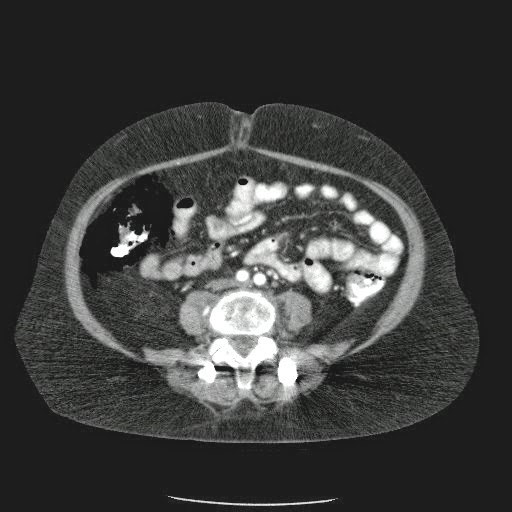

Caso Interesante #4

Adulto masculino, 1 semana de fiebre y malestar general.

¿Dónde esta ubicado el hallazgo?